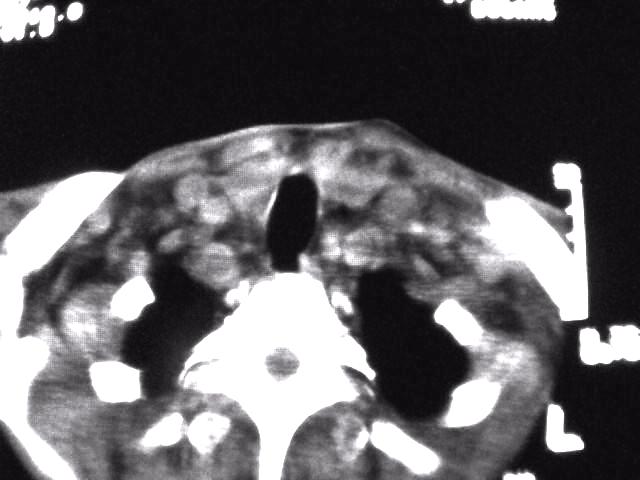

颈部层厚10mm间距10mm连续扫描及增强扫描共24层示:左侧下颈部胸锁乳突肌内侧区域内可见多发软组织结节,密度不均,内可见斑片状低密度区,大小不等,部分融合成块,左侧融合成一块者大约9.0x5.4,与周围肌肉、血管等结构界面不清,骨质未见明显浸润影。左侧锁骨下可见多个软组织结节,与周围界限尚清,左侧锁骨上窝内可见一大软组织肿物,大小约4.7x3.7cm,内密度欠均匀中心可见低密度区。

考虑:左侧颈部及双侧锁骨下多发淋巴结肿。非何杰金氏淋巴瘤可能性大,建议进一步检查。